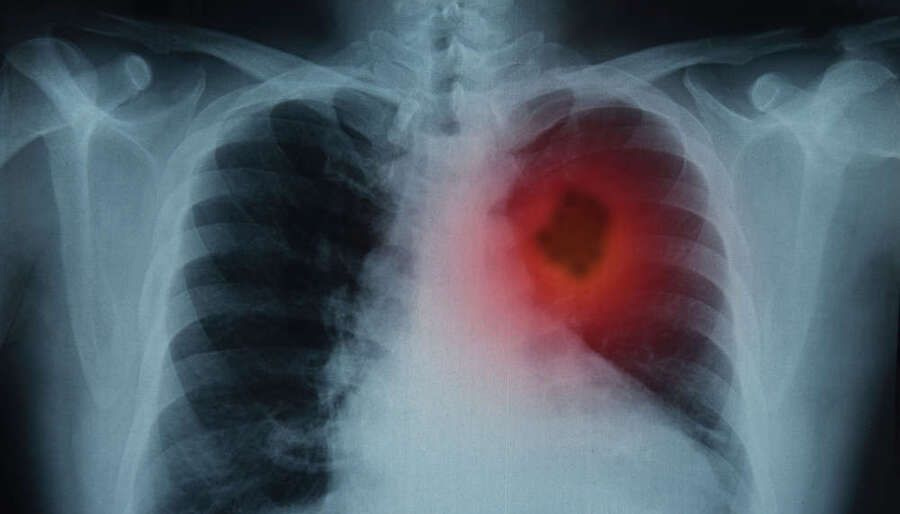

Μια νέα διεθνής επιστημονική μελέτη καταλήγει στο συμπέρασμα ότι η Covid-19 συνδέεται πιθανώς με αυξημένο κίνδυνο εμφάνισης καρκίνου του πνεύμονα, εγείροντας νέα ερωτήματα για τις μακροπρόθεσμες επιπτώσεις της πανδημίας.

Σύμφωνα με την ανάλυση δεδομένων από τη διεθνή βάση TriNetX, η οποία περιλαμβάνει ιατρικά αρχεία περισσότερων από 166.000 ατόμων, οι επιζώντες της Covid-19 εμφάνισαν υψηλότερα ποσοστά καρκίνου του πνεύμονα σε σύγκριση με μη μολυσμένα από τον SARS-CoV-2 άτομα.

Μεταξύ ενεργών καπνιστών, ο κίνδυνος ανήλθε στο 1,7% έναντι 1,4% στην ομάδα ελέγχου, ενώ στους πρώην καπνιστές καταγράφηκε 1,5% έναντι 1,2%. Ακόμη και στους μη καπνιστές, αν και τα ποσοστά ήταν χαμηλότερα, παρατηρήθηκε διαφορά (0,21% έναντι 0,18%).

Οι ερευνητές επισημαίνουν ότι δεν καταγράφηκε αντίστοιχη αύξηση σε άλλους τύπους καρκίνου, όπως του στόματος ή της ουροδόχου κύστης, γεγονός που ενισχύει την υπόθεση ότι η επίδραση του ιού εντοπίζεται κυρίως στους πνεύμονες.